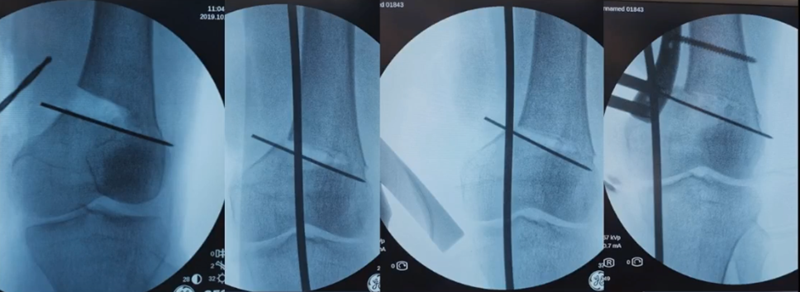

3、选择合页位置和截骨线

合页点的选择与HTO一样,通常需要尽可能接近畸形部位,既要有很好的骨质结构,还要有坚韧的软组织覆盖,以保证稳定性和术后有良好的血运。合页宽度不宜太长,通常保留在5mm。

合页点定位有两种方法,一种为定位在股骨外后髁上缘2mm位置,通常将此区域叫做“鹰嘴区”,以此为解剖标记法来定位合页点。

另一种通过导针从截骨入点向股骨外后髁后缘打出一条切线,此切线与外侧骨皮质的交点,也可作为合页点,这种方法称为导针法。这两种方法在手术之中是可以互为验证的。

合页点处于松质骨区,易形变区,如选择周边区域较脆易折断。另外合页点后方有小腿三头肌的附着点,有很好的的软组织和血运,综合来说作为合页非常合理。

合页点和截骨线已确定好,按照术前计划打入导针,测量截骨深度。

截骨过程中,不要求一次截骨到位,把合页深度全部截到,可以留最后一点,用钻头由前向后打出一排筛孔来,把合页端弱化,再去做闭合时就不容易折断了。